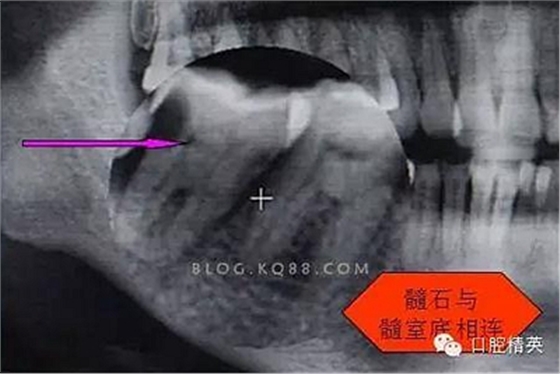

圖三

剛開始懷疑有增生的牙體組織,其實(shí)就是髓石。

3.開髓去腐后,髓腔基本就是這樣,在頰側(cè)近遠(yuǎn)中都有根管口顯示,初步用8號C+銼去試探性探查根管,沒有阻力感,以為就是c型根管,舌側(cè)用C+銼時有阻力感覺,接上測量儀去探查根管,以防C+銼探通后超出根尖孔,最后舌根長度16mm*15號K銼(16.5mm*8號C+銼),機(jī)擴(kuò)F2。接下來著重頰側(cè)的根管尋找,后來在頰側(cè)近遠(yuǎn)中插入K銼時總覺得K銼尖段都指向一個位置,感覺不對,再次讀X線片,后來發(fā)現(xiàn)術(shù)前沒有仔細(xì)查看X線片,以及未回顧這位患者年齡,也就忘記牙齒的增齡性改變的含義。髓腔之所以小或者不清楚,一個因?yàn)槟挲g增加的原因二是因?yàn)檠例X長期受到外界物理化學(xué)刺激所導(dǎo)致髓腔變小,甚至沒有髓腔顯影。本病例患者,髓腔有大概顯影,但髓室里好像有增生的牙體組織,其實(shí)就是髓石。并且和髓室底相連接。如果不注意,有可能按常規(guī)預(yù)備方法進(jìn)行預(yù)備。